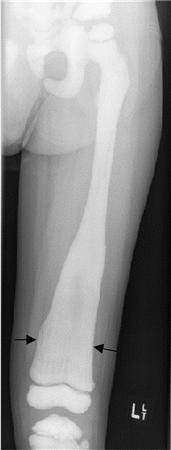

Melorheostosis

Benign condition of abnormal periosteal bone formation

“dripping candle wax” appearance with dense hyperostosis that flows along the cortex of the bone